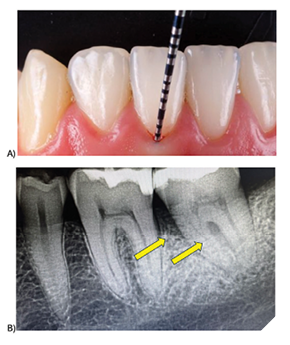

Periodontal disease remains one of the most prevalent yet preventable chronic conditions in adults, affecting nearly half of the adult population at some point in their lives. Yet for decades, dentists have relied on tools that largely tell the story of damage after it has already happened, through radiographs and periodontal probing, rather than giving an early warning before irreversible destruction occurs (Fig. 1). This diagnostic gap has meant that millions of patients worldwide progress to moderate or severe disease before interventions begin.

Fig. 1